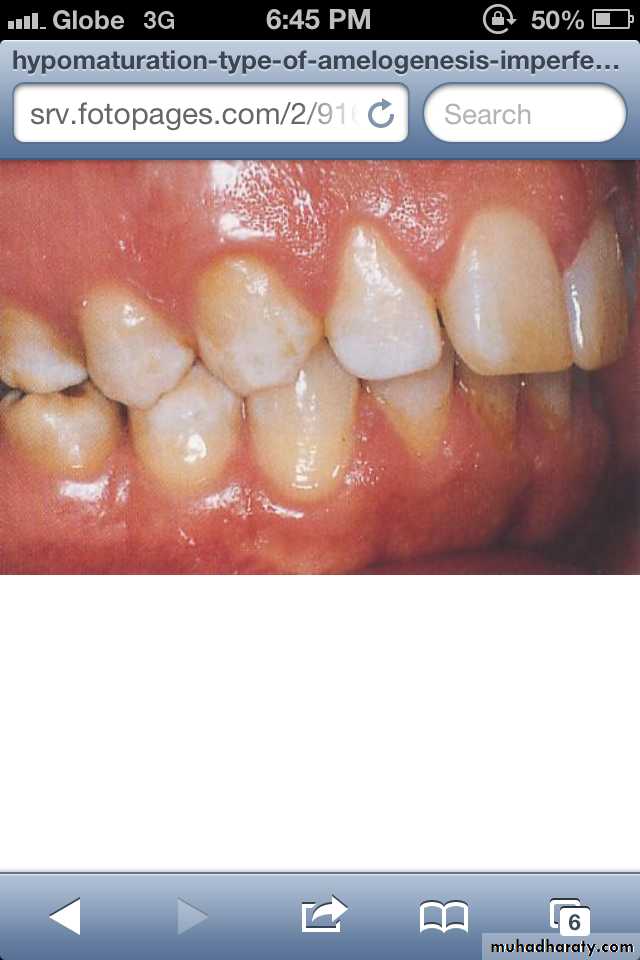

Hypomaturation Amelogenesis Imperfecta:

*Enamel is normal in form on eruption but:

opaque.white to brownish-yellow.

softer than normal.

tends to chip from underlying dentin.

Radiographically:

Affected enamel exhibits radiodensity similar to dentin.